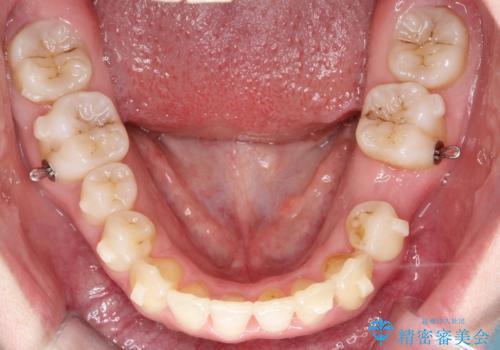

左下5番は先天性欠損のため乳歯は抜歯しインプラントにて欠損補綴しています。